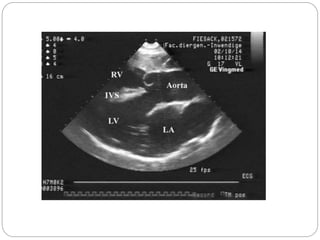

Echocardiography in TOF

Parasternal long-axis view

 Left and right ventricular size/function

 Degree of aortic override

 override of the aortic root over the

ventricular septal defect should be less

than half of the aortic diameter

 Analysis of the ventricular septal defect

 magnitude and direction of shunting

across the VSD

 Confirmation of aorto-mitral

continuity

 absence of the fibrous continuity between

the aortic and mitral valves is inconsistent

with tetralogy of fallot, and may be

suggestive of double outlet right ventricle

(DORV)